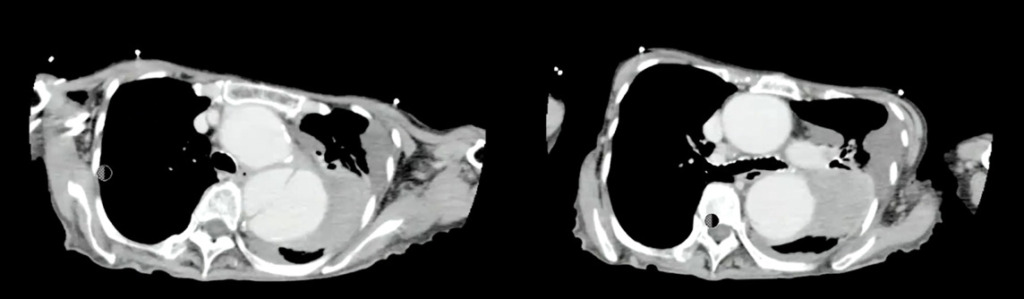

紹介先にて造影CTを施行。

転院先で造影検査を行い、胸部大動脈破裂と大動脈解離StanfordBの診断となっています。

胸部大動脈の著明な拡張と、その周囲に高吸収域を認める(大動脈破裂、contained ruptureを示唆)。

この症例はimpending ruptureではないんですよね 。もうすでに破れてるcontained ruptureに一致します。破れてるんだけど肺が押してるという状況です。もうすでに破れそう切迫破裂じゃなくてすでに破れてるという状況なので 、そういうのも合わせて手術適用ないという判断がされたと考えます。